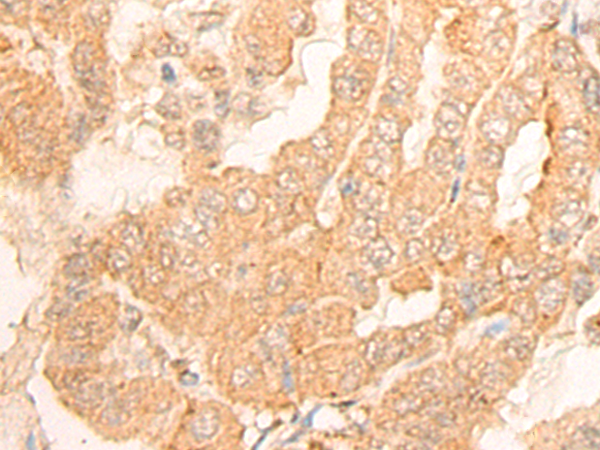

ELISA, IHC |

IHC Positive control: |

Human thyroid cancer; |

IHC Recommended dilution: |

25-100 |